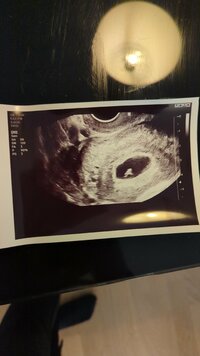

Tänään kävin ultrassa, kun pelästyin kadonneita oireitani. Halusin saada mielenrauhan, ja sen onneksi sain! Meidän pikkuinen olikin hieman pienempi, nyt noin 6+0-1 (piti olla 6+3), mutta syke löytyi ja kaikki näytti hyvältä ❤️